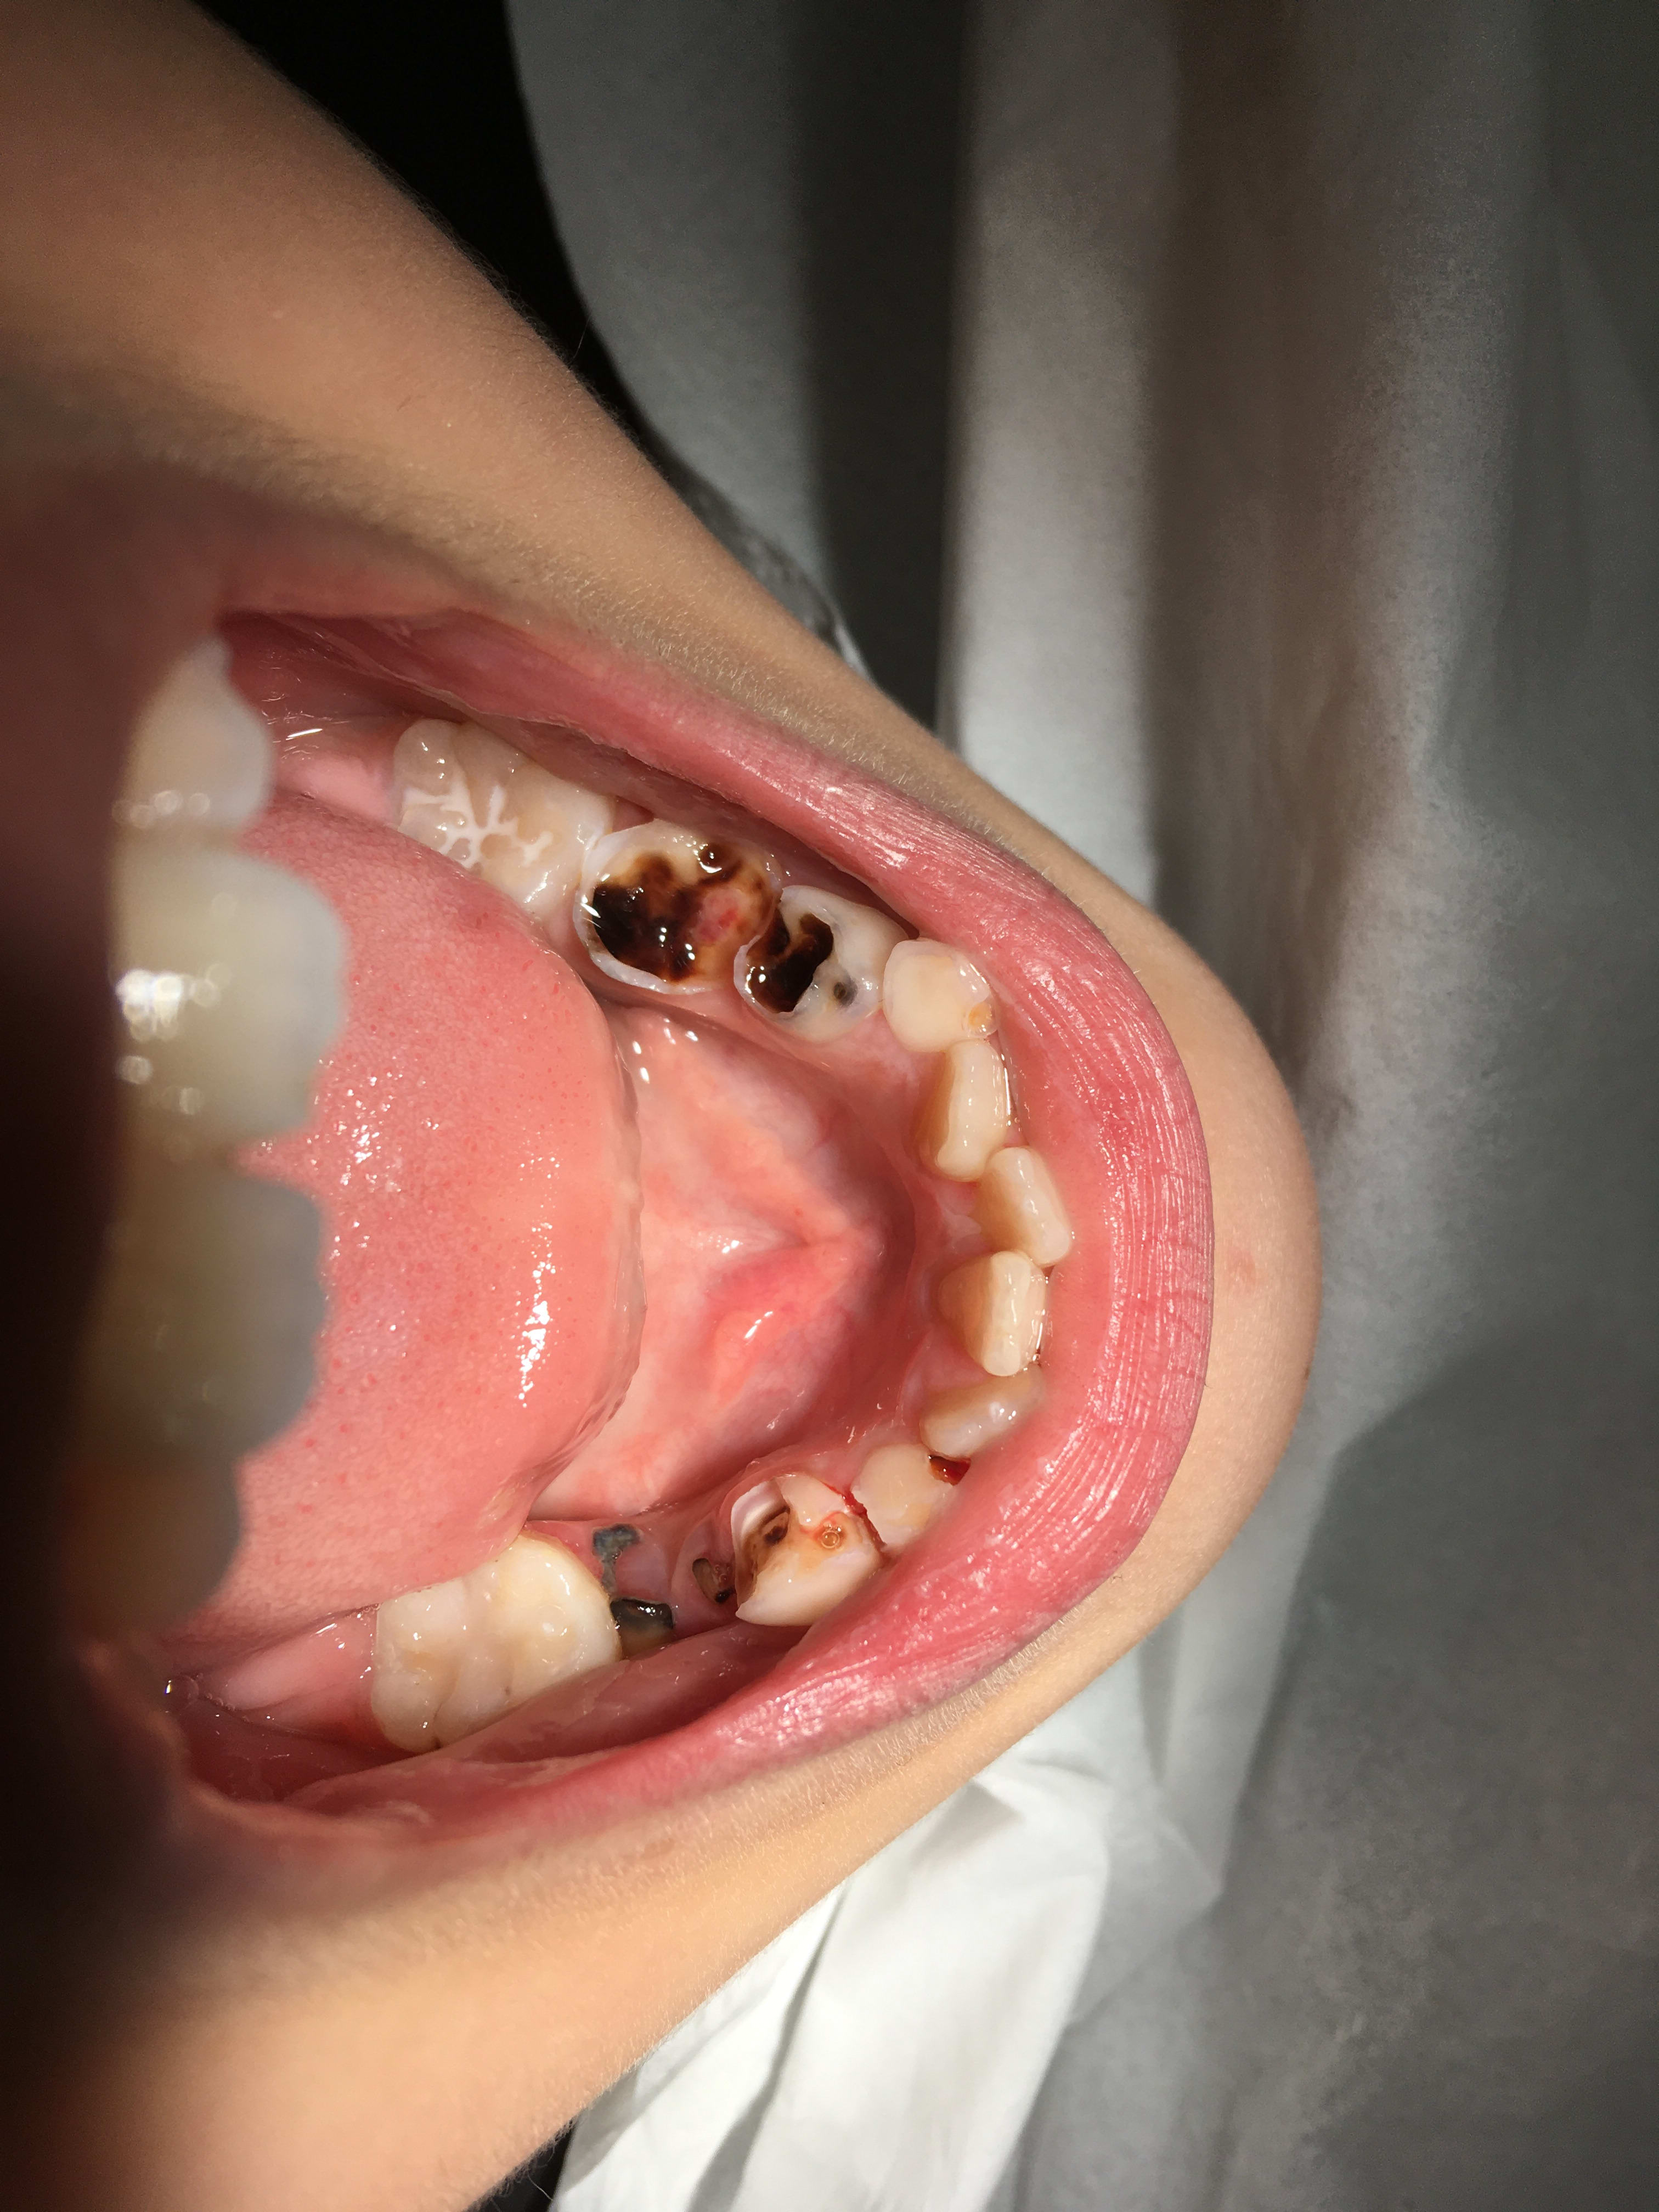

Bon allez, comme on se refroidit, patient numéro 2 !

Avant d'enchaîner, je tiens à préciser que je vais vous présenter des patients d'une seule et même semaine, c'est plus rigolo.

Enfant de trois ans, adressé par un confrère qui ne se sentait pas de gérer mais qui adresse en donnant mes coordonnées (bien, bien !) au lieu de l'habituel "faut voir un pédodontiste, démerdez-vous" (en sous-entendu dans le texte)

Les parents font donc 75 kilomètres pour venir me voir. Aller aussi loin pour voir un nul, faut vraiment qu'ils vivent dans un trou paumé, un désert médical. Ah non, 350k habitants dans leur agglomération, ah ouais, chaud ! Et aucun pédo dans leur coin qui prend des nouveaux patients ! Sixième puissance mondiale hein, faut lsavoir !

Enfant tout sourire, s'installe sur le fauteuil, ouvre grand la bouche et surprise.

Premier point: pas de plaque dentaire. J'ai été surpris.

Bon, classique, carie du biberon, c'est tout éclaté de partout. Test au froid, oulalala, ça couine, bichette, petite larmichette, elle n'ouvre plus la bouche, je négocie cinq minutes, elle rouvre, on recommence. Ca va etre drôle les soins.

Et donc je leur explique que vu le chantier, faudra faire ça sous MEOPA avec le surcoût que ça implique pour eux vu qu'on est parti pour plein de séance. Et à 150km la séance + 150€ de dépassement + le fait qu'on rentre tout juste dans l'indication d'anesthésie générale, on va réfléchir à cette possibilité.